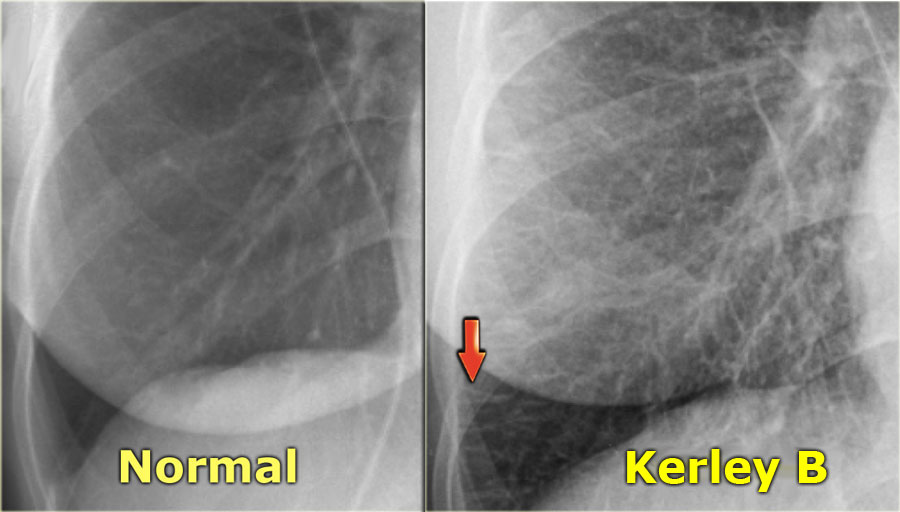

نضع بين ايديكم مجموعة الصور الاضافية على السلايدات التي تم شرحها في X-ray session :

Kerley B line